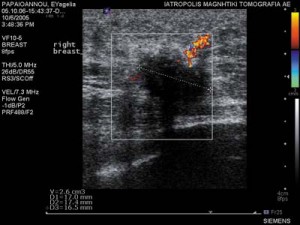

● Υπερήχοι υψηλής ευκρίνειας με ή χωρίς την έγχυση σκιαγραφικού